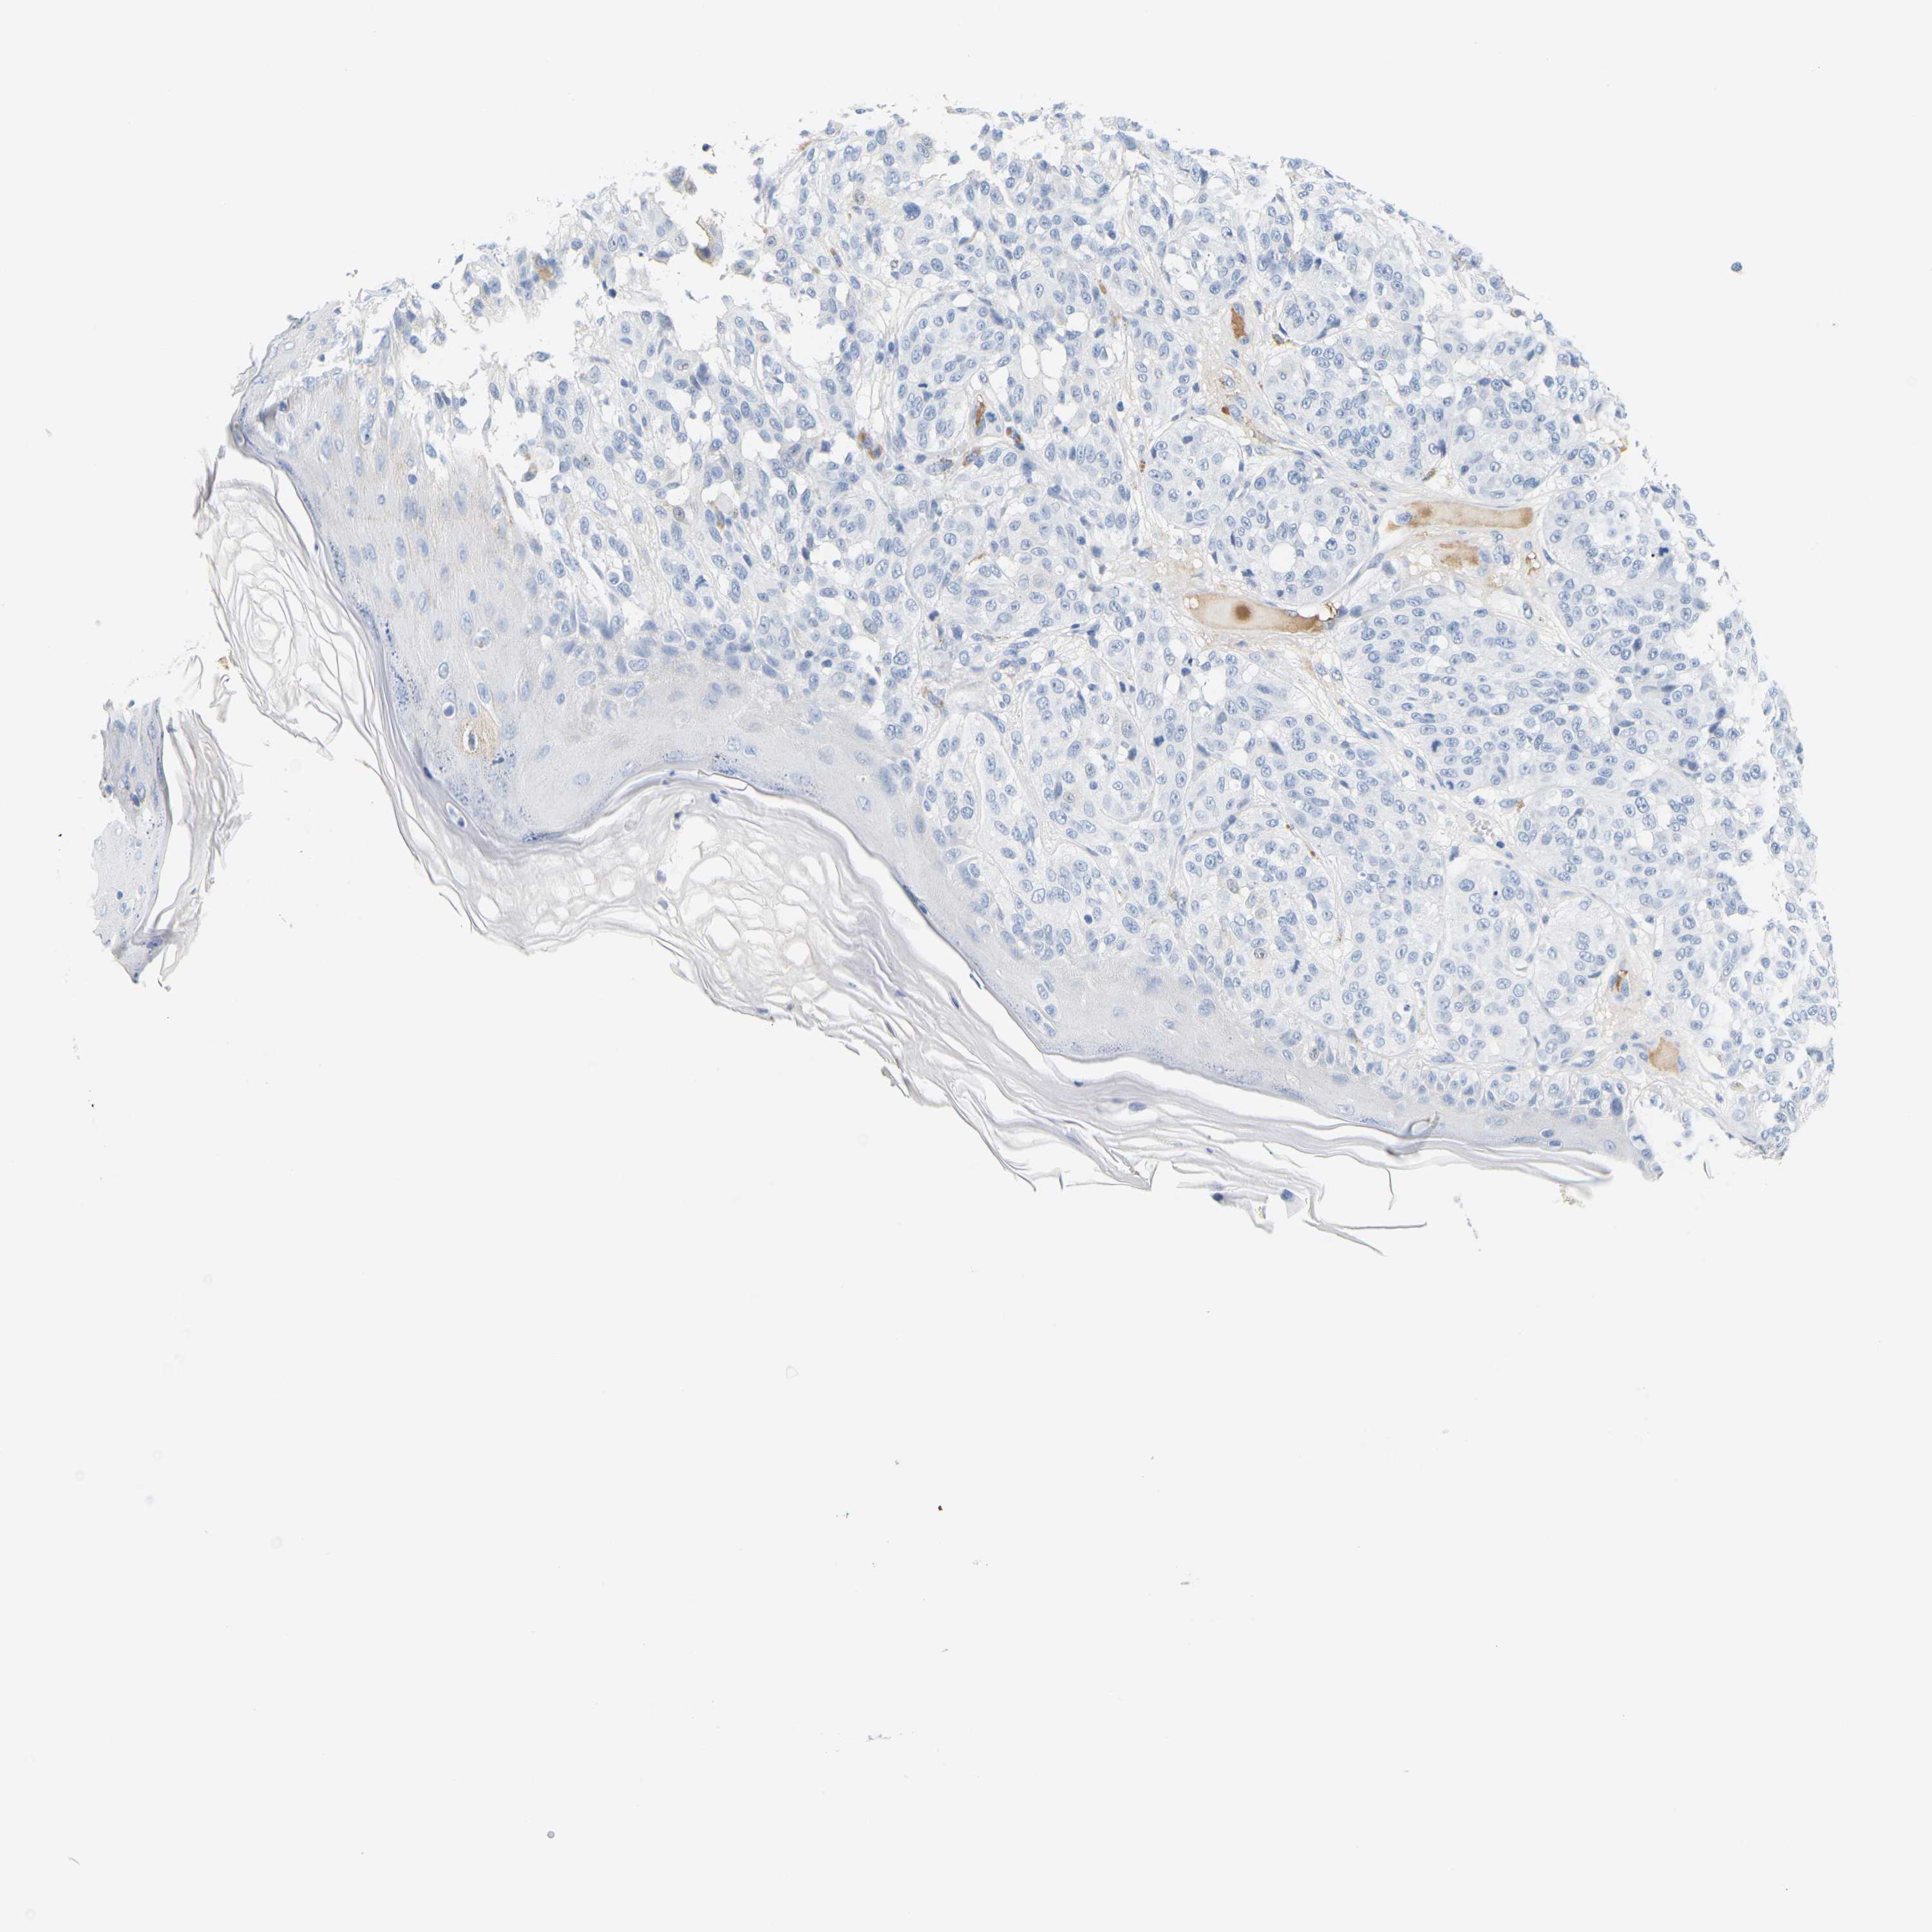

MELANOMA - Protein expressioni

A mouse-over function shows sample information and annotation data. Click on an image to view it in a full screen mode. Samples can be filtered based on level of antibody staining by selecting one or several of the following categories: high, medium, low and not detected. The assay and annotation is described here.

Note that samples used for immunohistochemistry by the Human Protein Atlas do not correspond to samples in the TCGA dataset.

Antibody stainingi

Antibody staining in the annotated cell types in the current human tissue is reported as not detected, low, medium, or high, based on conventional immunohistochemistry profiling in selected tissues. This score is based on the combination of the staining intensity and fraction of stained cells.

Each image is clickable and will lead to virtual microscopy that enables deeper exploration of all samples and also displays staining intensity scores, fraction scores and subcellular localization as well as patient and tissue information for each sample.

HPA049793

CAB016070

CAB080297

CAB080298

CAB080299

Staining

High

Medium

Low

Not detected

Intensity

Strong

Moderate

Weak

Negative

Quantity

>75%

75%-25%

<25%

None

Location

Nuclear

Cytoplasmic/membranous

Cytoplasmic/membranous,nuclear

Malignant melanoma, NOS

Malignant melanoma, Metastatic site